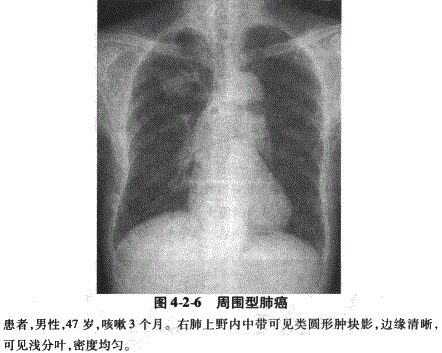

2.周围型肺癌:周围型肺癌是指肿瘤发生于肺段以下支气管的肺癌,可见于各种组织学类型,其中主要是细支气管肺泡癌和腺癌。早期肺癌X线表现为直径小于2.0cm的结节影,主要X线征为分叶征,边缘毛糙、模糊,胸膜凹陷征,结节影内可有小透光区,称为空泡征或小泡征。进展期肺癌肿块直径多在3.0cm以上,一般密度均匀,较大肿瘤可因坏死液化形成空洞,肿瘤边缘毛糙,可见分叶征象,肿瘤侵犯支气管可引起阻塞性肺炎或肺不张,表现为肿瘤周围斑片状或片状阴影,邻近胸膜的病变可牵拉脏层胸膜引起胸膜凹陷征,发生肺内转移表现为肺内多发结节影(图4-2-6)。